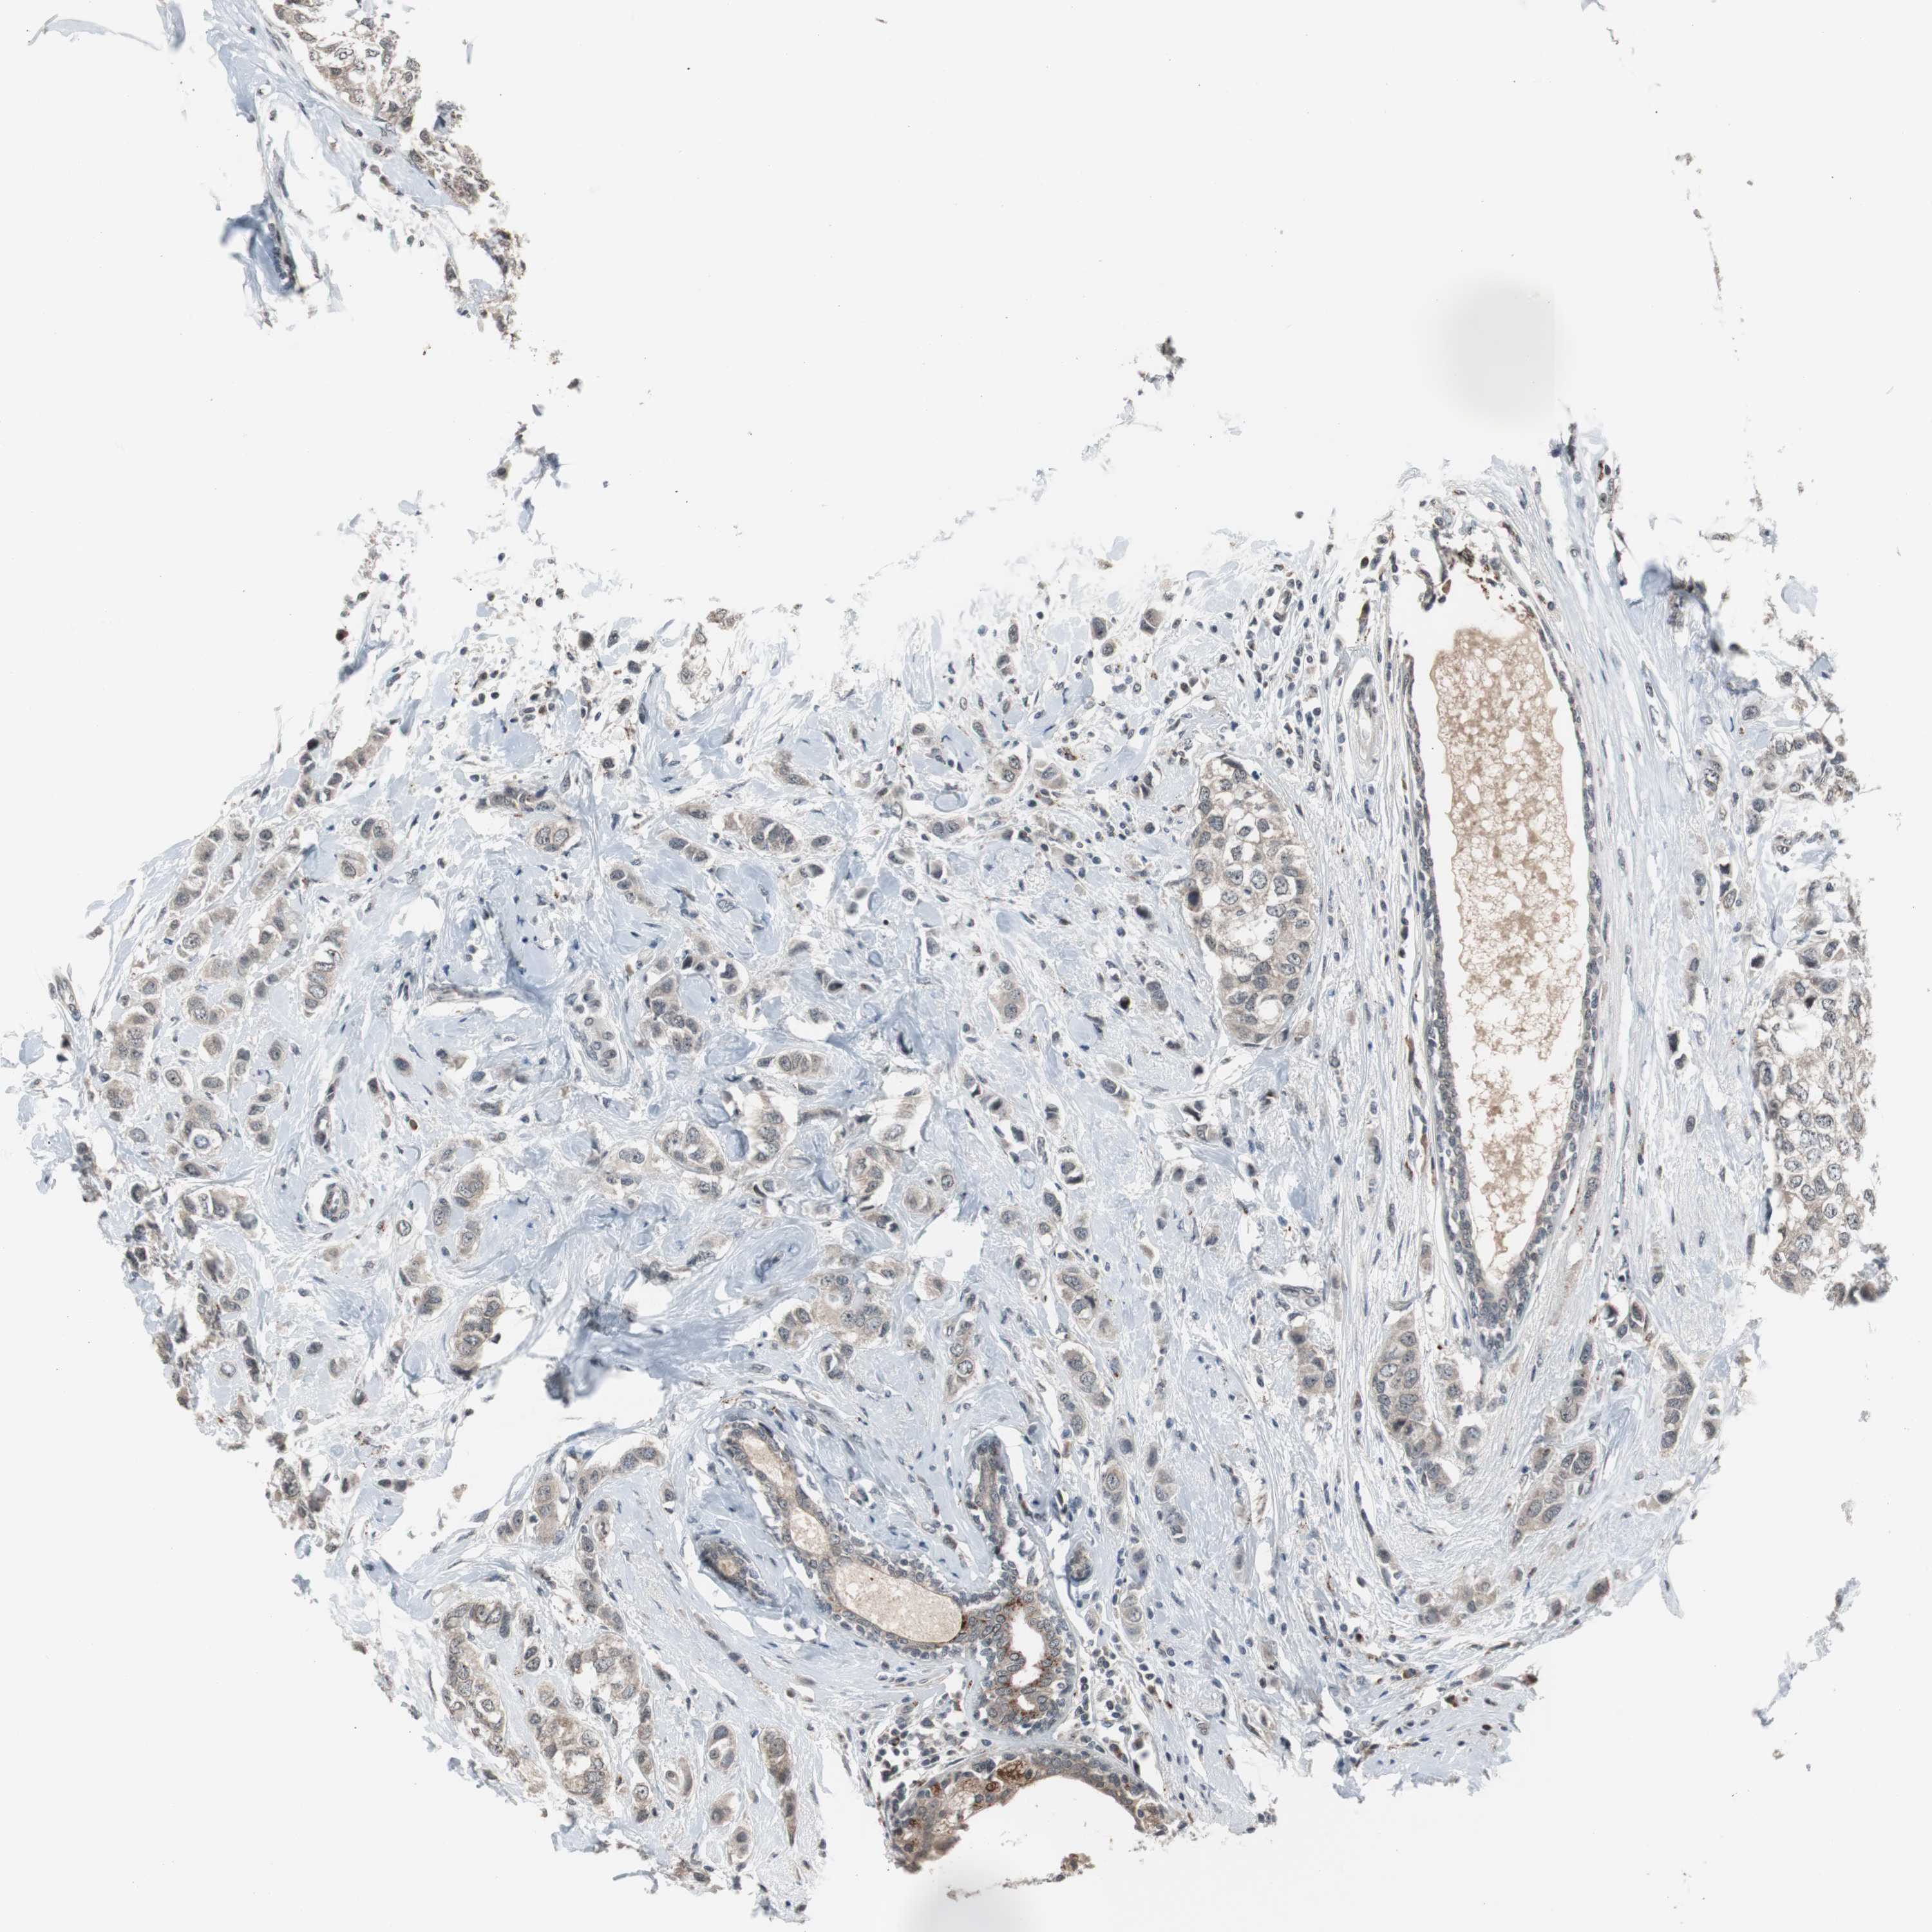

BRCA TCGA BRCA VALIDATION PROTEIN EXPRESSION

ANTIBODIES

AND

VALIDATION